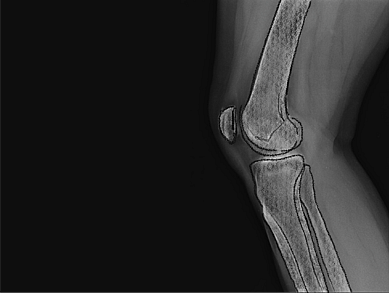

Partial knee replacement

Targeted robotic surgery for partial knee replacement, preserving healthy tissue while relieving pain and restoring movement.